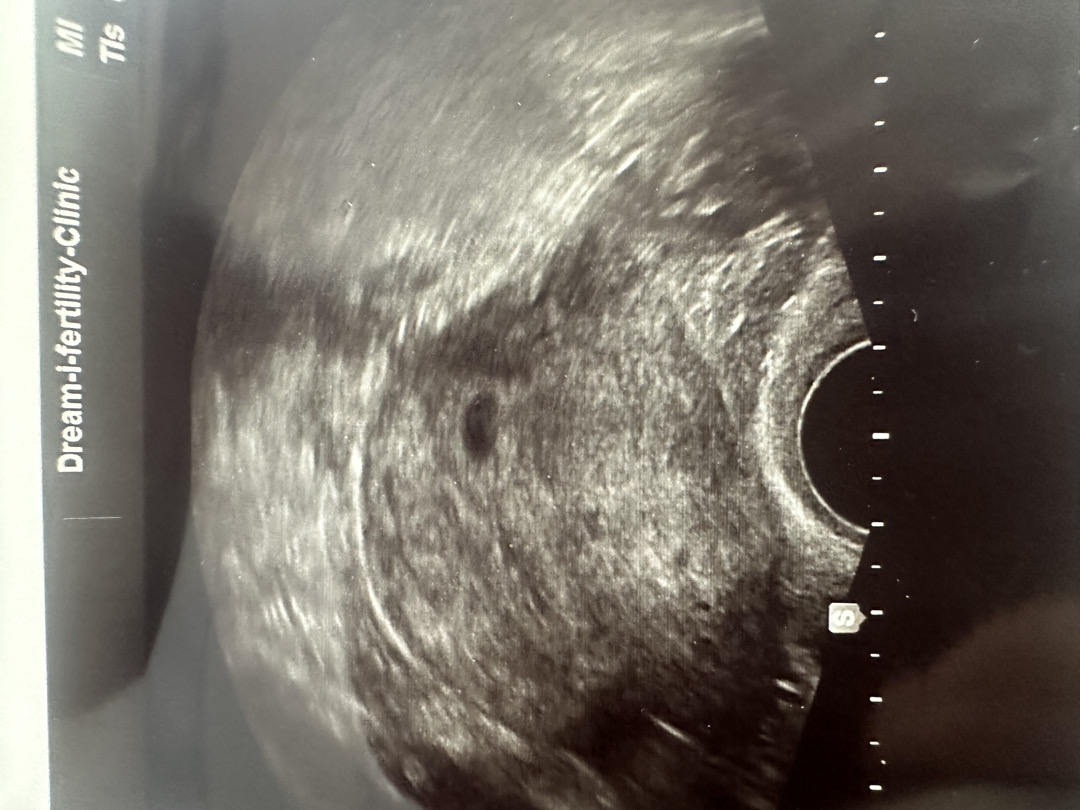

5주차 초음파 아기집

이제 이번주 월요일에 5주차라고 아기집 보고 왔는데요. 다른 사람들은 엄청 아기집도 크던데… 저처럼 초음파 작게 나오신 분들 있나요? 괜히 걱정이 되네요ㅠㅠ

저 4주차 6일에 초음파 봤는데 아기집 0.5cm라고 했구 딱 5주차 정도 크기라고 하셨어요 ㅋ 넘 걱정 안 하셔도 될 거 같아요 ㅋ